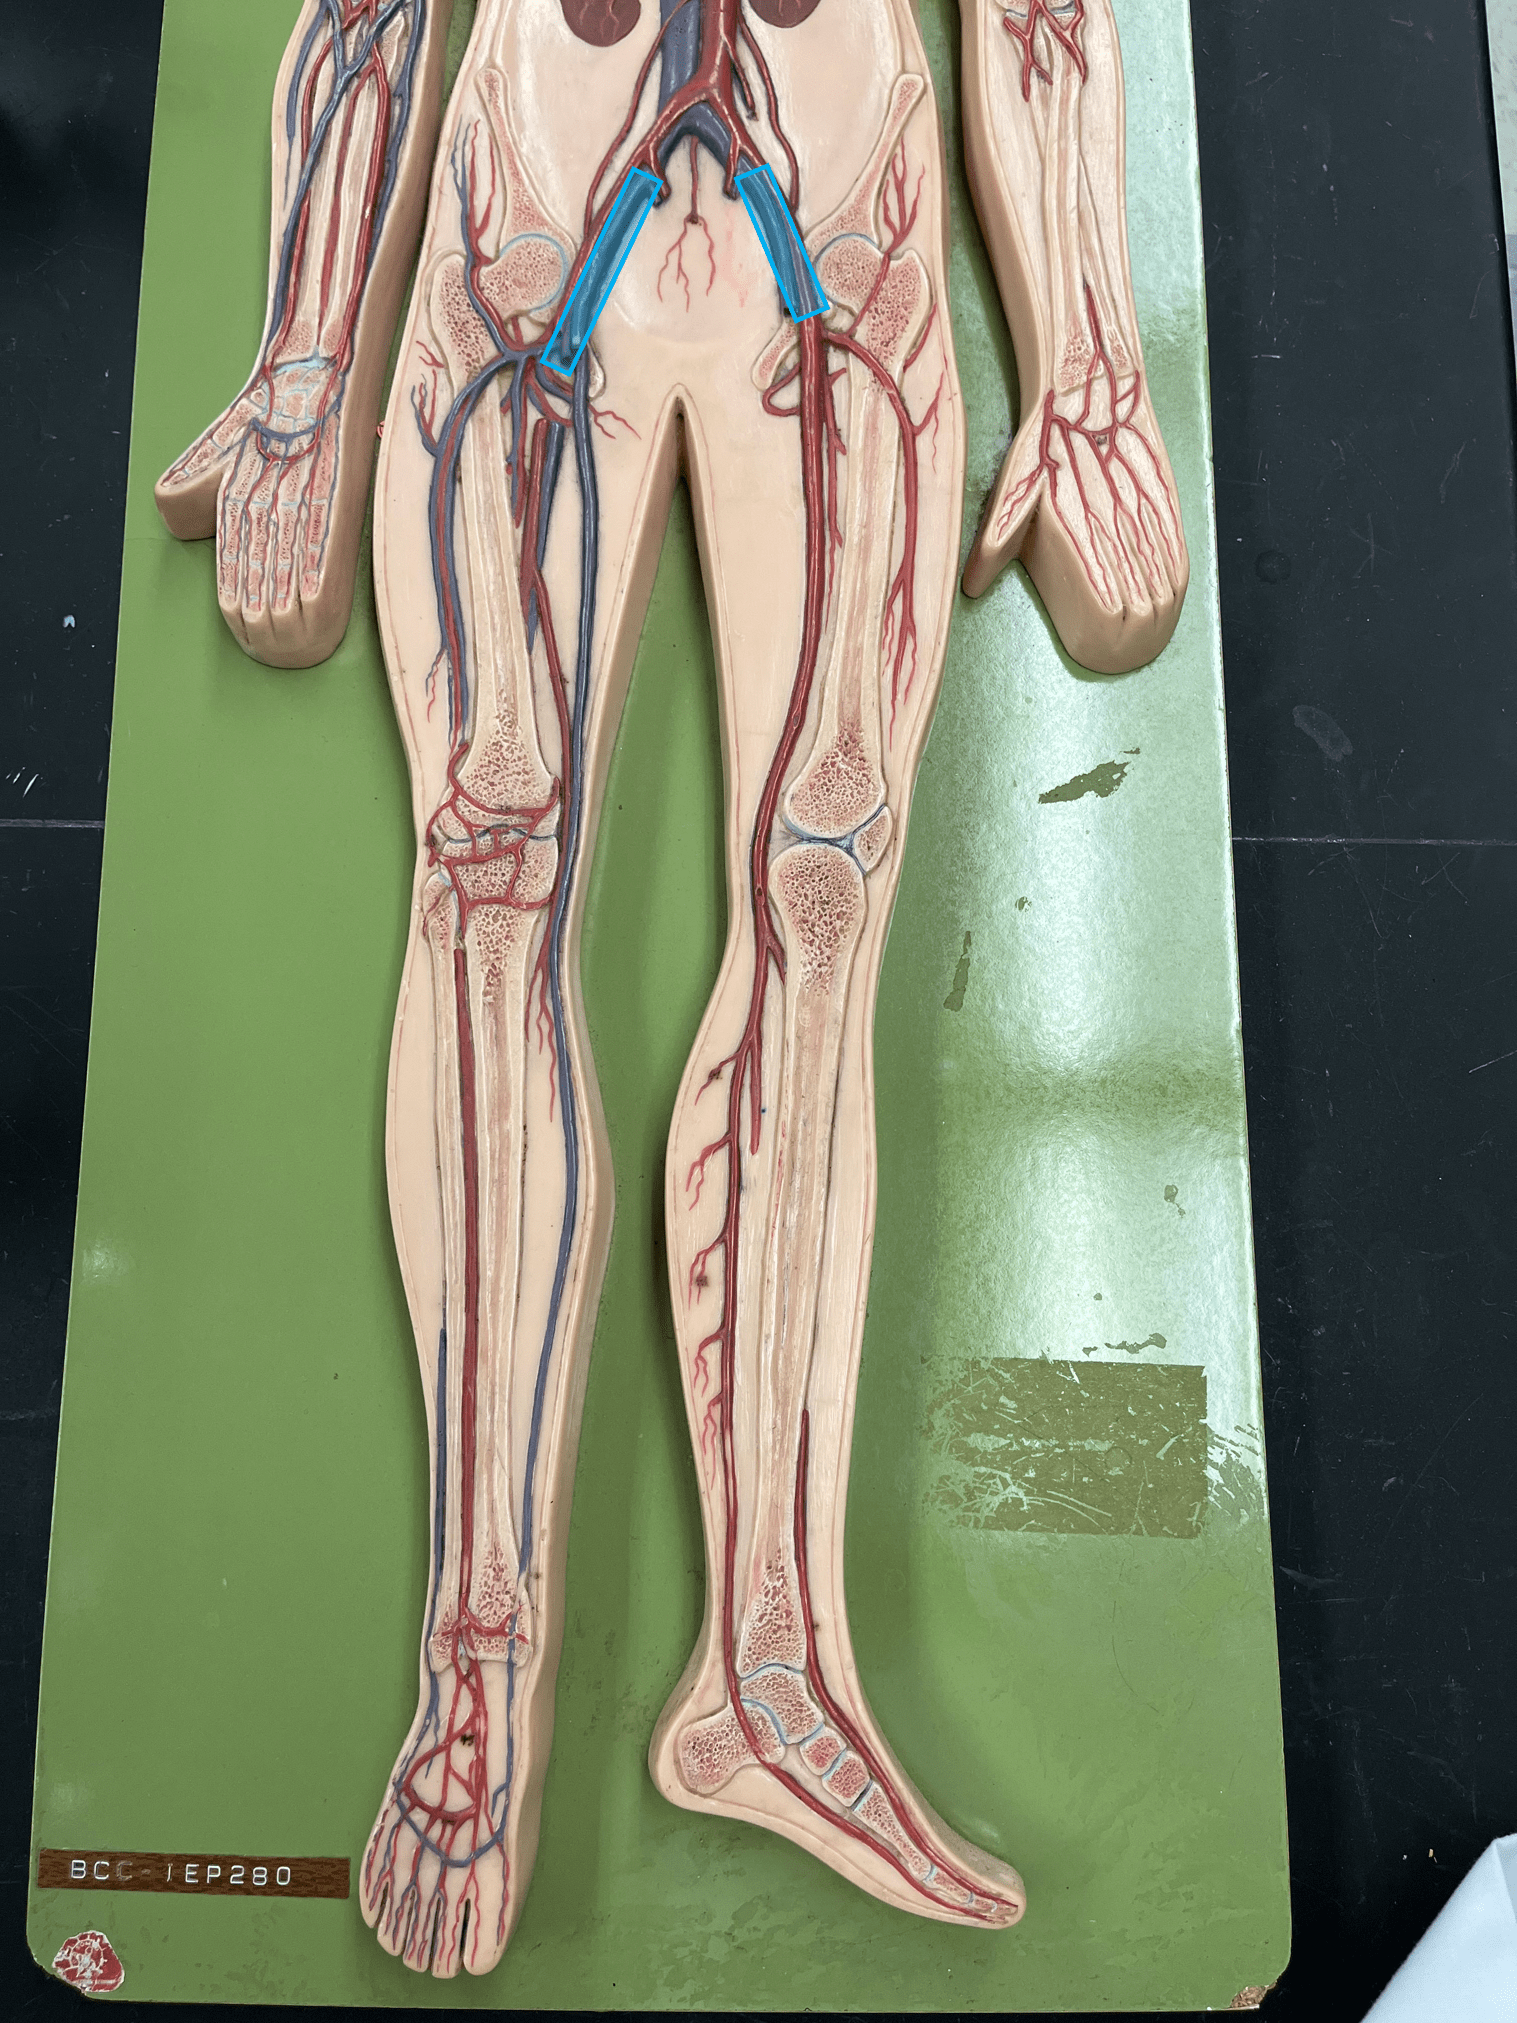

11

New cards

endothelium

• Part of the tunica interna.

• Composes a smooth inner surface of the vessel.

• Composes a smooth inner surface of the vessel.

12

New cards

valve

• Found in some veins.

• Establishes unidirectional flow of blood.

• Establishes unidirectional flow of blood.

13

New cards

common carotid artery

• An artery of the head and neck.

• Originates from the brachiocephalic trunk (R.) or the aortic arch (L.).

• Supplies the head and neck through its branches.

• Originates from the brachiocephalic trunk (R.) or the aortic arch (L.).

• Supplies the head and neck through its branches.